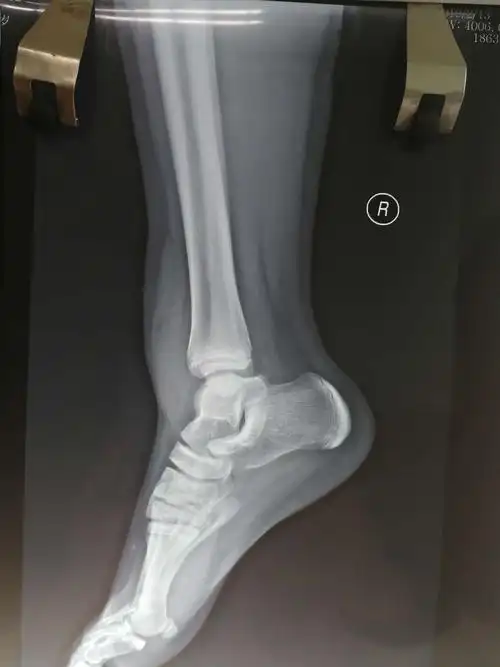

张豪,男,12岁,内外踝骨折